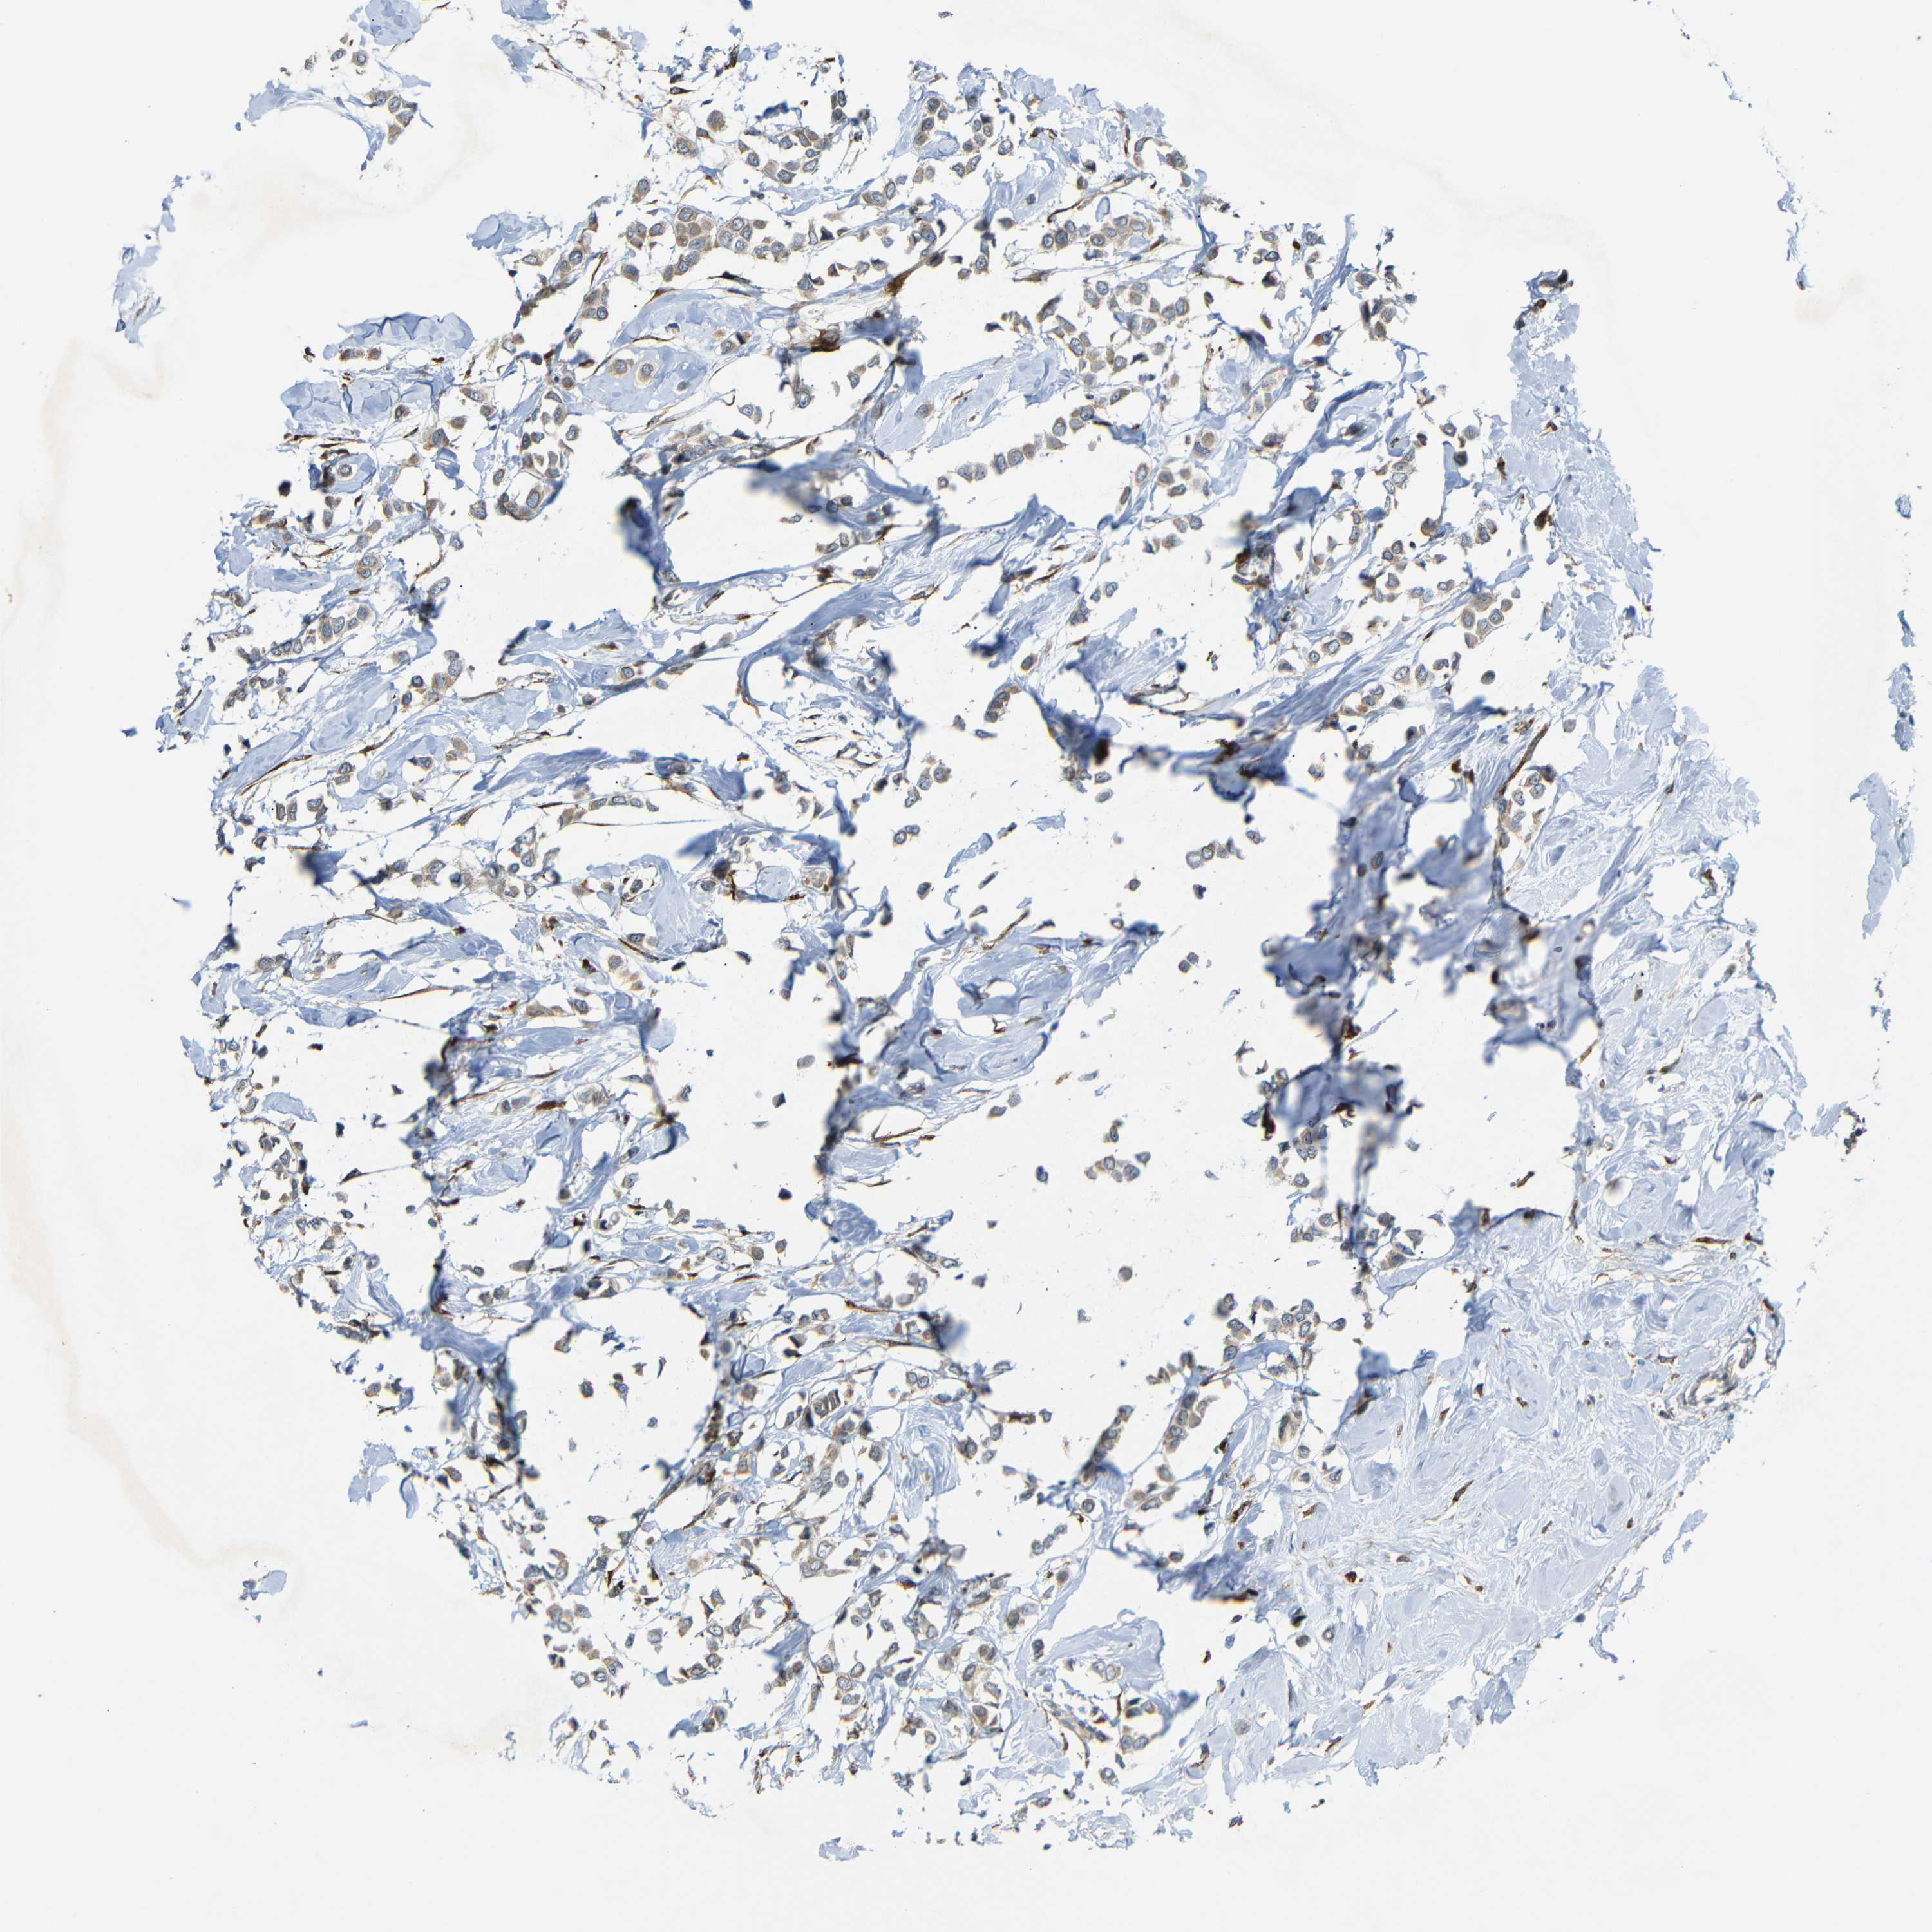

CANCER BREAST CANCER Show tissue menu

BRCA TCGA BRCA VALIDATION PROTEIN EXPRESSION